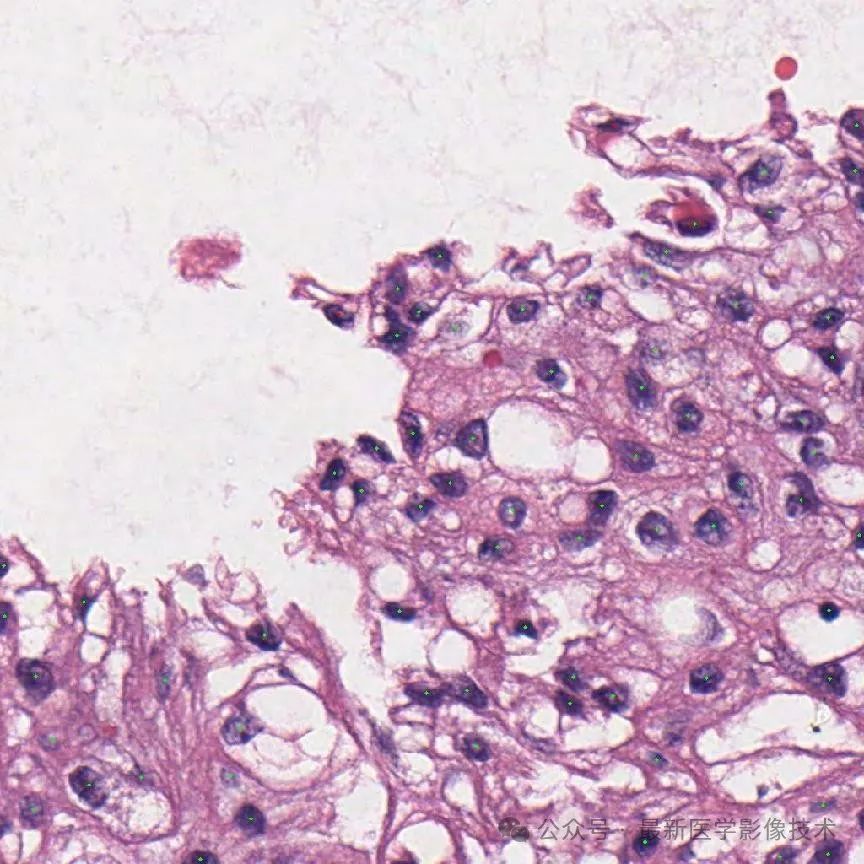

5、验证集部分分割结果

左图是原始图像,中间是金标准结果,右图是预测结果。

组织分割结果